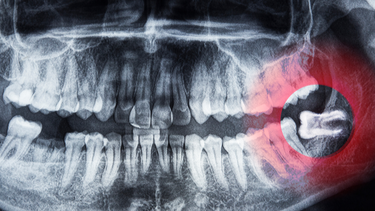

Viêm lợi trùm do vị trí mọc răng khôn

Răng khôn nằm ở vị trí trong cùng của hàm, thường mọc sâu trong bờ lợi và không trồi lên hoàn toàn như các răng khác. Khi ăn uống hoặc chải răng, phần răng này dễ cọ sát vào nướu, gây đau rát và tổn thương mô mềm. Theo thời gian, sự ma sát liên tục khiến lợi sưng đỏ, phồng rộp và dễ viêm nhiễm.

Viêm lợi trùm do hướng mọc răng khôn

Răng khôn là chiếc răng mọc cuối cùng nên thường không còn đủ chỗ để mọc đúng hướng. Vì vậy, nhiều người gặp tình trạng răng khôn mọc lệch, mọc nghiêng, thậm chí mọc ngầm trong nướu. Khi răng mọc sai hướng, lợi phía trên không thể mở ra hoàn toàn, dễ trùm lên răng và tích tụ vi khuẩn. Vùng lợi này khó được làm sạch, dẫn đến sưng đau, viêm nhiễm kéo dài và gây khó chịu trong sinh hoạt hằng ngày.